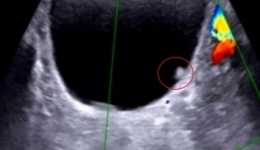

沉默的杀手:肾癌,你了解多少?